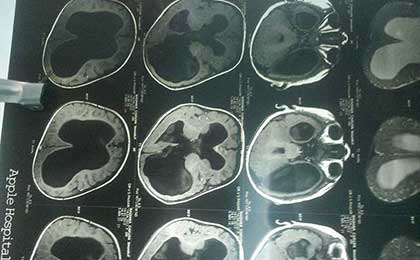

Pre OP CT